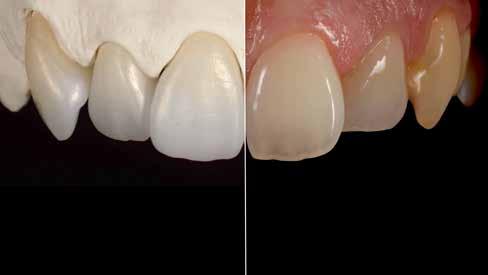

Interdiszciplináris fogászati kezelés myofunkcionális készülék, alignerek és protetikai ellátás alkalmazásával

MED. DENT Abradált frontfogakkal rendelkező felnőtt páciens interdiszciplináris kezelése

6. ábra: Balra: A szinterezett monolitikus cirkónium-dioxid koronák, Jobbra: Természetes modell.

7. ábra: Balra: A végeredmény Initial Lustre Pastes ONE égetéssel, Jobbra: Természetes fogak.